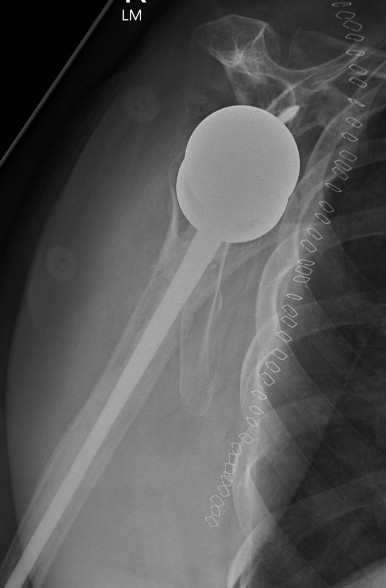

Dislocated Reverse TSRDislocated Reverse TSR Lateral

disdis

Early dislocation issues

Soft tissue tension  Axillary nerve palsy Component position  Component size

Humeral distalization

- increased liners

- longer humeral body

Inferior base plate  / inferior impingement

Increased glenosphere size increases jump distance

Glenoid lateralization

- lateralized glenosphere

Subscapularis